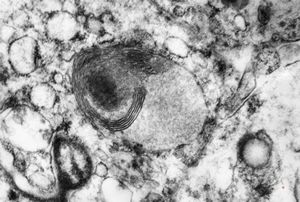

M,6m. | myelinoid inclusions in cerebral neuron - Nieman-Pick disease

M,6m. | myelinoid inclusions in cerebral neuron - Nieman-Pick disease